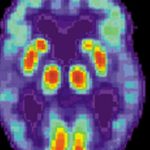

Un team di ricercatori in Cina ha creato diverse scimmie rhesus transgeniche aggiungendo un gene umano coinvolto nella crescita del cervello al genoma delle scimmie. Nell’ articolo pubblicato sulla National Science Review, il gruppo descrive il suo lavoro e i test condotti sulle scimmie dopo la loro nascita.

I ricercatori riportano che nessuna delle scimmie aveva cervelli più grandi del normale, ma tutte hanno superato la media dei test di memoria e delle capacità di elaborazione.

Per questo motivo, la maggior parte dei ricercatori non è disposta a partecipare a tale ricerca, anzi, uno dei ricercatori del team in Cina, un americano della North Carolina University, ha avuto ripensamenti. Ha suggerito che la creazione di scimmie che hanno alcuni aspetti del potere del cervello umano “è eticamente impensabile”. Afferma di aver solo assistito alla RM per i test del volume cerebrale.